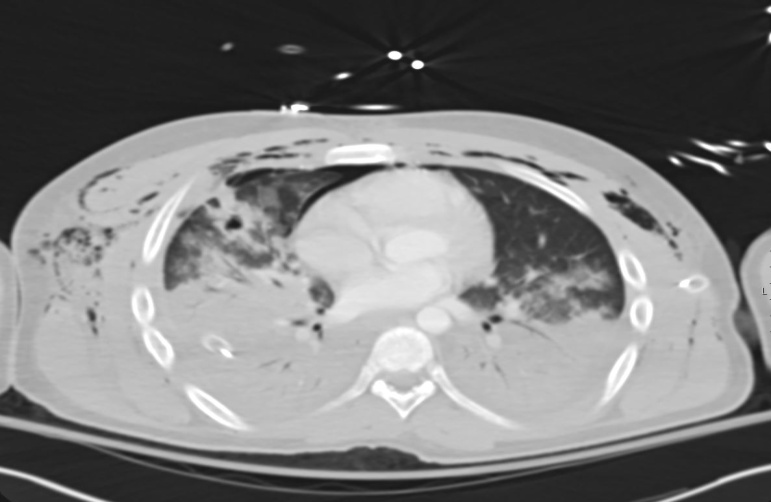

The microscopic examination of the sputum sample after treatment with 40% KOH and special stains revealed no fungal elements. The sputum was cultured in blood, chocolate, MacConkey and Sabouraud dextrose agar. The chest X-ray showed bilateral consolidation in the right lower lobe with veiling air space opacities (fig. 2). The chest CT showed bilateral scattered ground glass opacities and multifocal inhomogeneous consolidation with small cavitary lesions in the middle lobe. It was consistent with pneumonia, extensive subcutaneous emphysema and minimal pneumomediastinum. (fig. 3). Patient was not at risk for contact with Tuberculosis or fungal infection; hence lymph proliferative disorders or Nocardiosis was strongly considered based on imaging morphology. The modified acid-fast staining for sputum and BAL samples showed filamentous weak acid-fast bacilli resembling Nocardia species (fig. 4). The patient did well with Trimethoprim and sulfamethoxazole combination with linezolid and spO2 monitoring, and discharged later. Further follow-up ensured about completion of three months of antibiotics and improvement based on clinical findings and radiologically.

Fig. 3: The chest CT showed scattered ground glass opacities bilaterally and multifocal inhomogeneous consolidation with small cavitary lesions in the middle lobe (pneumonia, extensive subcutaneous emphysema and minimal pneumomediastinum)